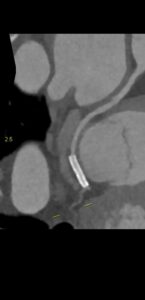

Figurile 1 si 2: reconstrucție multiplanară din examinarea inițială cu evidențierea stenozei severe de la nivelul arterei descedente anterioare (la examinarea coronarografică a fost reclasificată că stenoză moderată și nu a fost stentată)

Figurile 4 si 5: reconstrucție multiplanară din examinarea recentă cu evidențierea subocluziei / ocluziei de la nivelul arterei descedente anterioare, in evolutie intre cele doua examinari